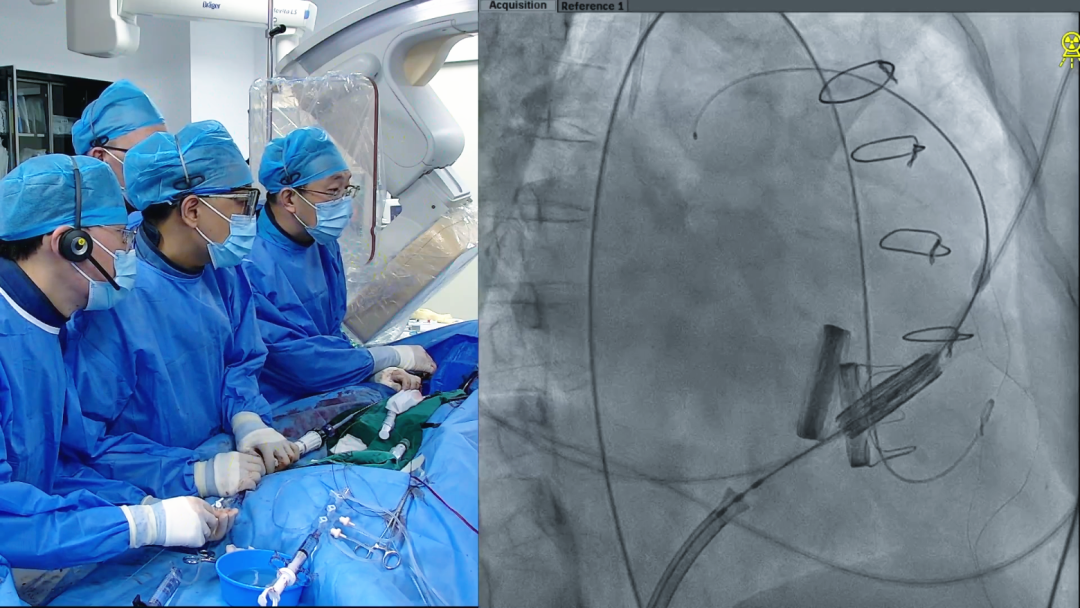

手术过程

1.术中经股静脉入路,送入指引导管、导丝,成功跨瓣,建立导丝轨道。

2.进行预扩张。球囊打开时未见明显腰征,预扩张球囊顺利打开梗阻瓣膜。

3.经股静脉入路送入16F E-sheath可扩张导管鞘,随后送入SAPIEN 3球扩瓣1输送系统,由于肺动脉入路朝上走,无需调弯,顺利跨瓣,将SAPIEN 3球扩瓣送入预定位置。精准定位后,以160次/分快速起搏,并保证1:1完全夺获,缓慢释放瓣膜。术后超声检查结果显示即刻跨瓣压差从术前9mmHg降至3mmHg,顺利完成瓣膜释放,回撤导管、导丝。